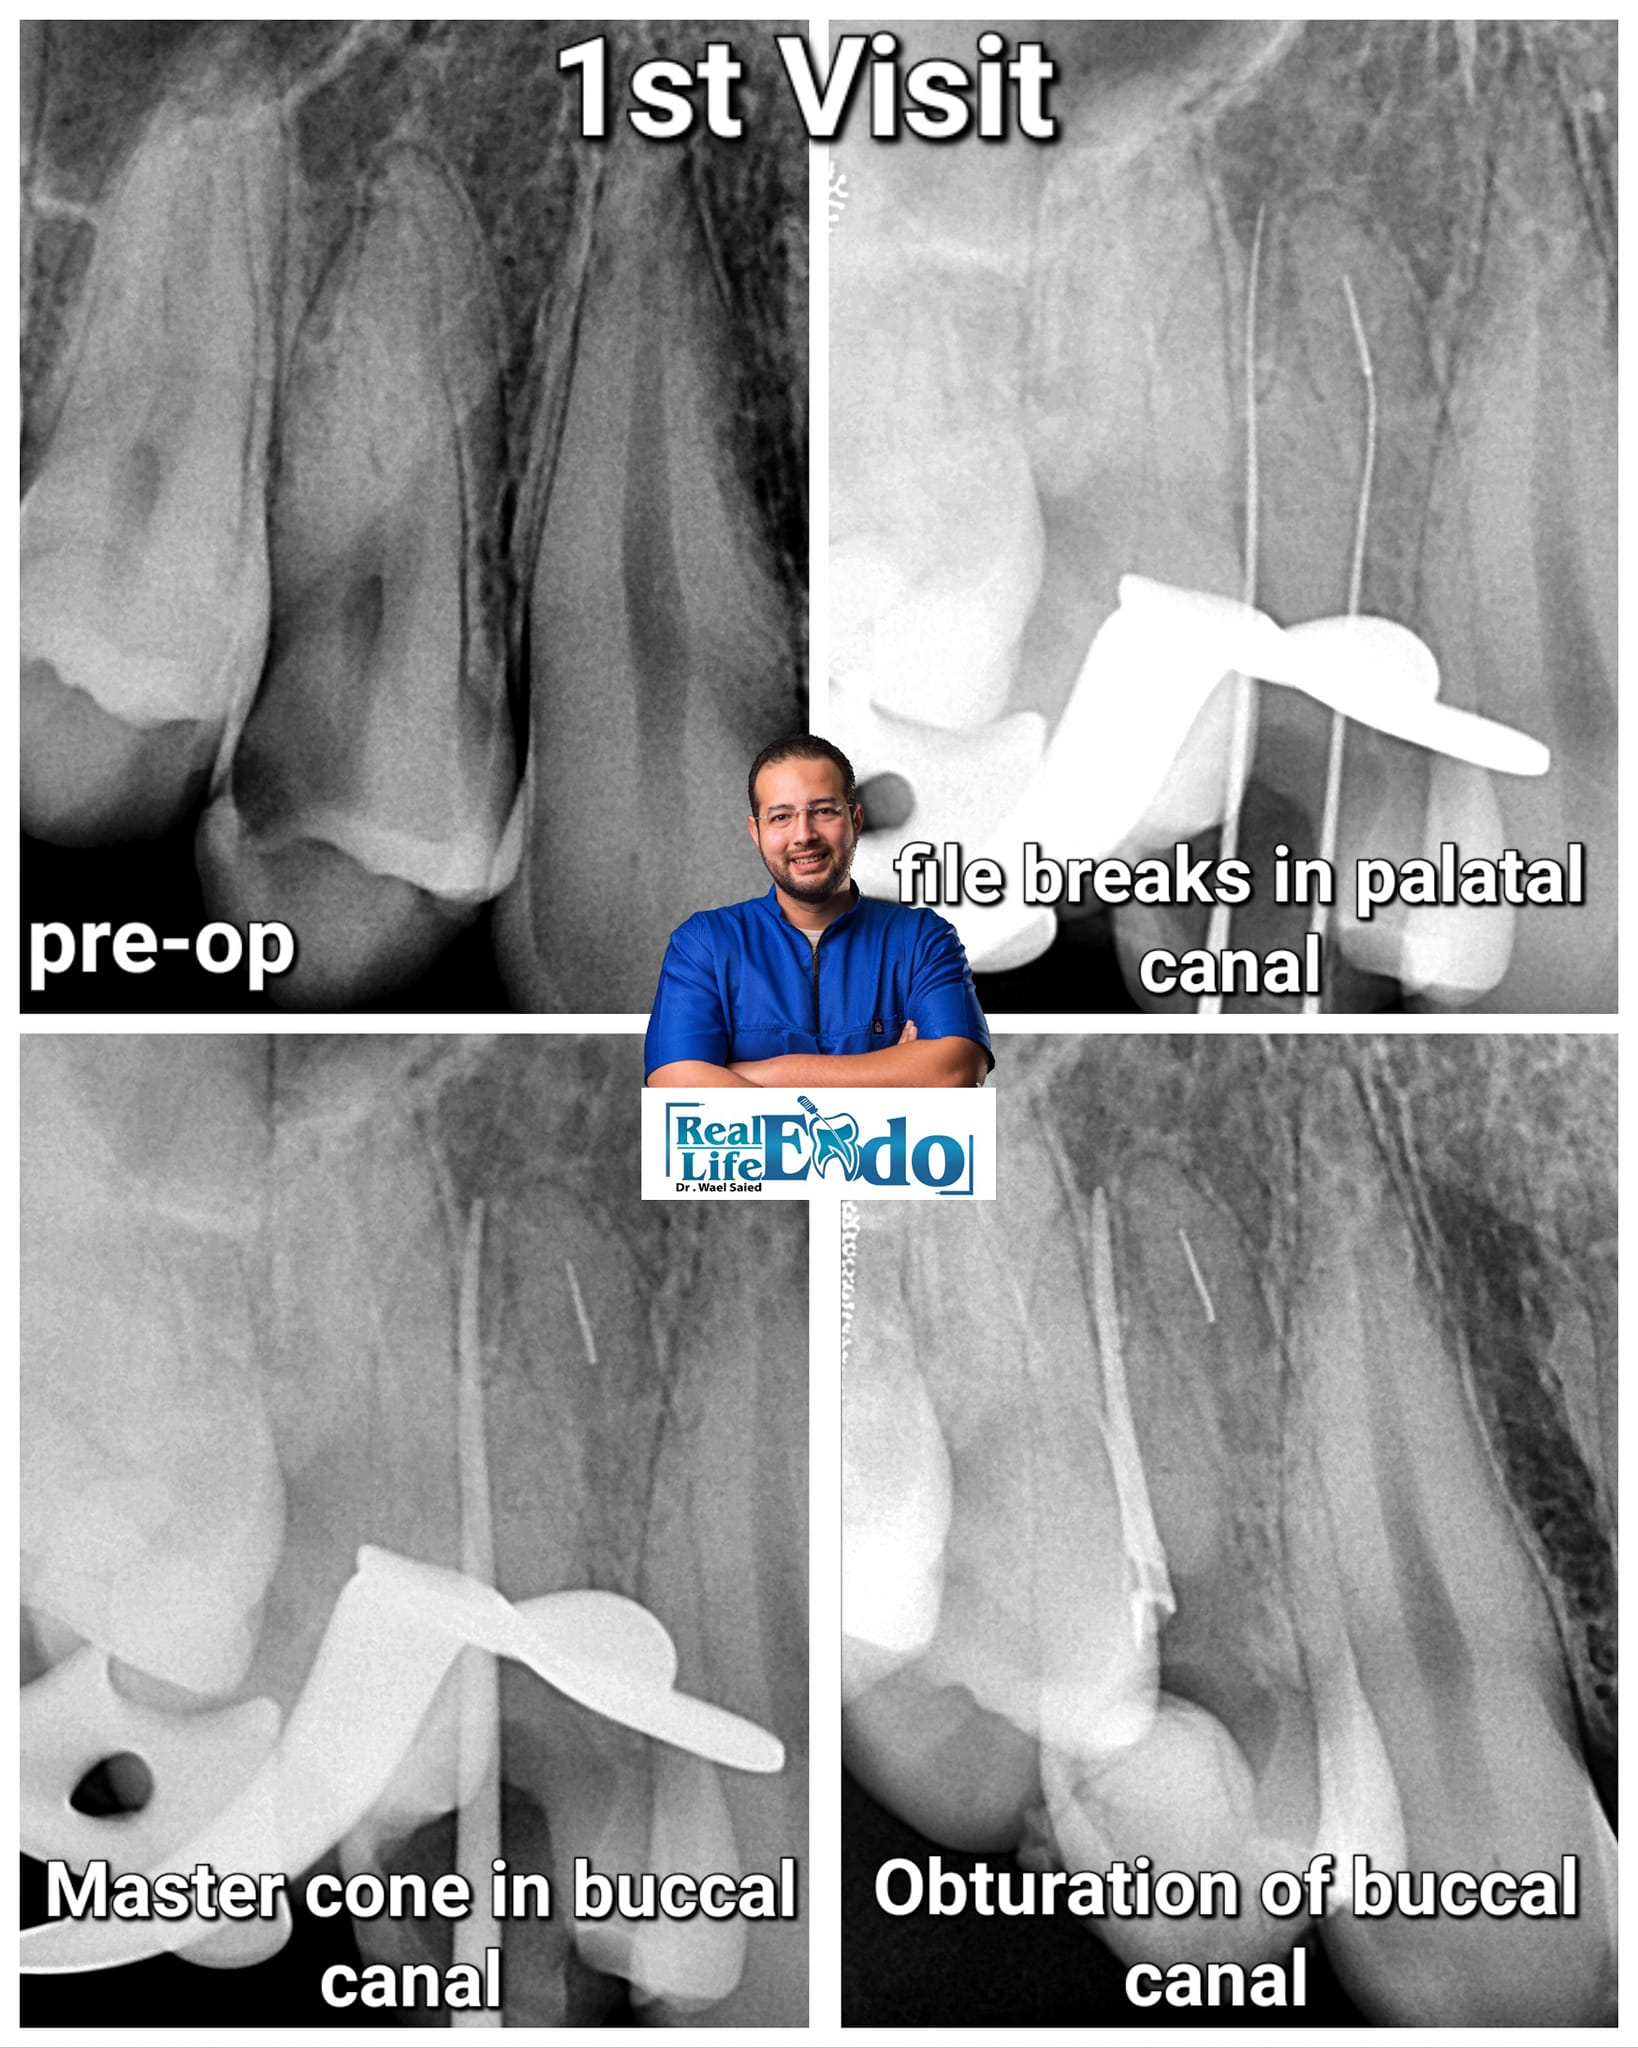

for me Broken file retrieval is more predictable than bypass

but as the BF located more apically.... I prefer bypass over retrieval

for me dentin Preservation is a 1st priority....as BF locate more apically that means more dentin to remove for retrieval

bypass is more conservative option

another tip: if any errors happens during RCT try to finish the easy part of RCT and delay the management of the errors as possible to a 2nd visit

to start fresh... and have a plan and proper tools

using File Sequence Cycling technique for bypass